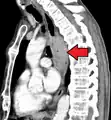

![]() | |

| Endoscopic image of an esophageal adenocarcinoma | |